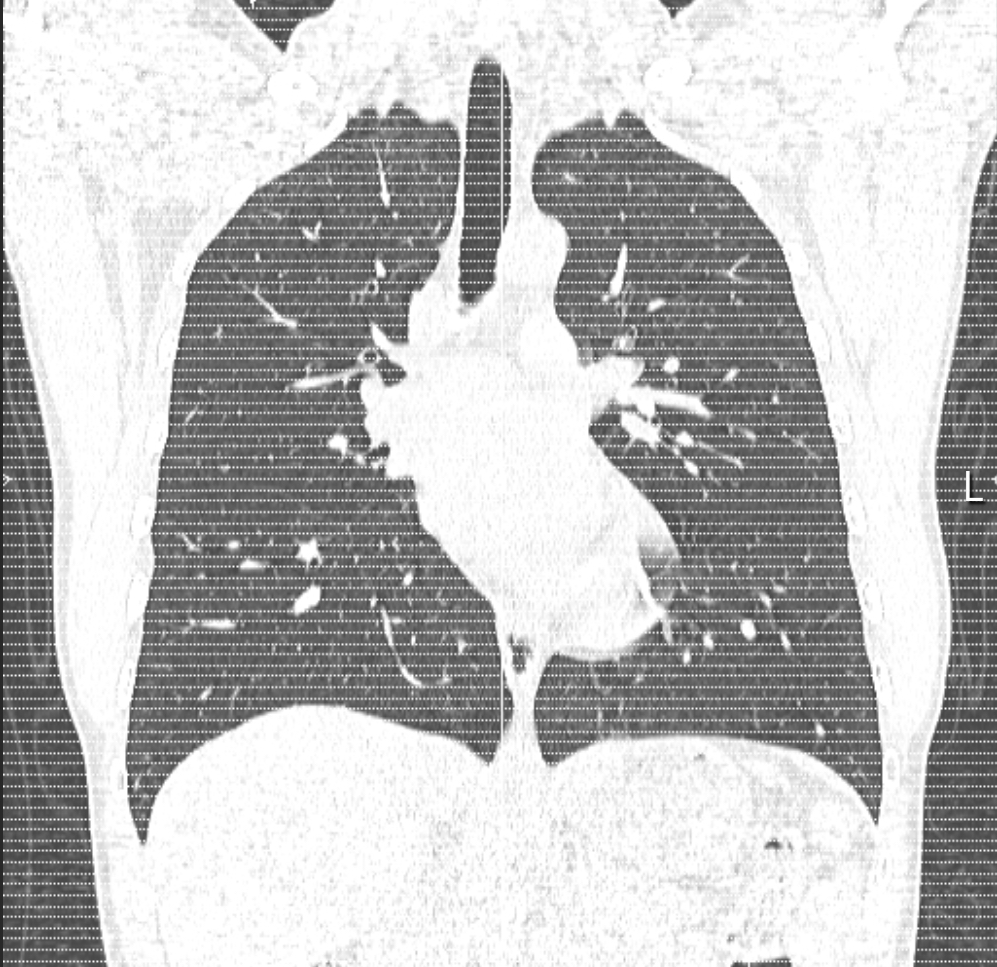

Imaging, overall, has been pretty minimal, which I’m definitely grateful for. So far, I’ve had two chest X-rays and a CT scan, all focused on my lungs.

The initial X-ray and CT scan were done around the same time earlier this year. While some pulmonologists might say the CT scan was a bit excessive, mine wanted to be sure we had a solid understanding of what shape my lungs were in before starting any kind of treatment or monitoring.

I agreed, because unfortunately, one of the other main areas the genetic mutation I have can affect is the lungs, so I wanted to make sure everything looked okay on that front. We also figured that it would be beneficial to have a baseline for comparison in case any issues come up down the line.

Both results (which I’ll share below) came back clear. I wasn’t expecting anything different, since I was still running without any issues, but it was still nice to get some good news at a time where it felt like good news was in short supply.

With my admission date approaching, we did one final chest X-ray a few weeks ago just to make sure everything still looked good, and it does. As you can imagine, being able to largely maintain my health throughout this whole process has meant a lot to me, and it’s always reassuring when the data backs that up.

As for the actual experience, the X-rays felt quick and straightforward, but the CT scan was definitely more daunting. Even if you’re not claustrophobic, some discomfort is to be expected. The doughnut type machine they use is loud and definitely a little nerve-wracking, but I kept reminding myself they wouldn’t be putting me through it unless the information they were gathering was important.